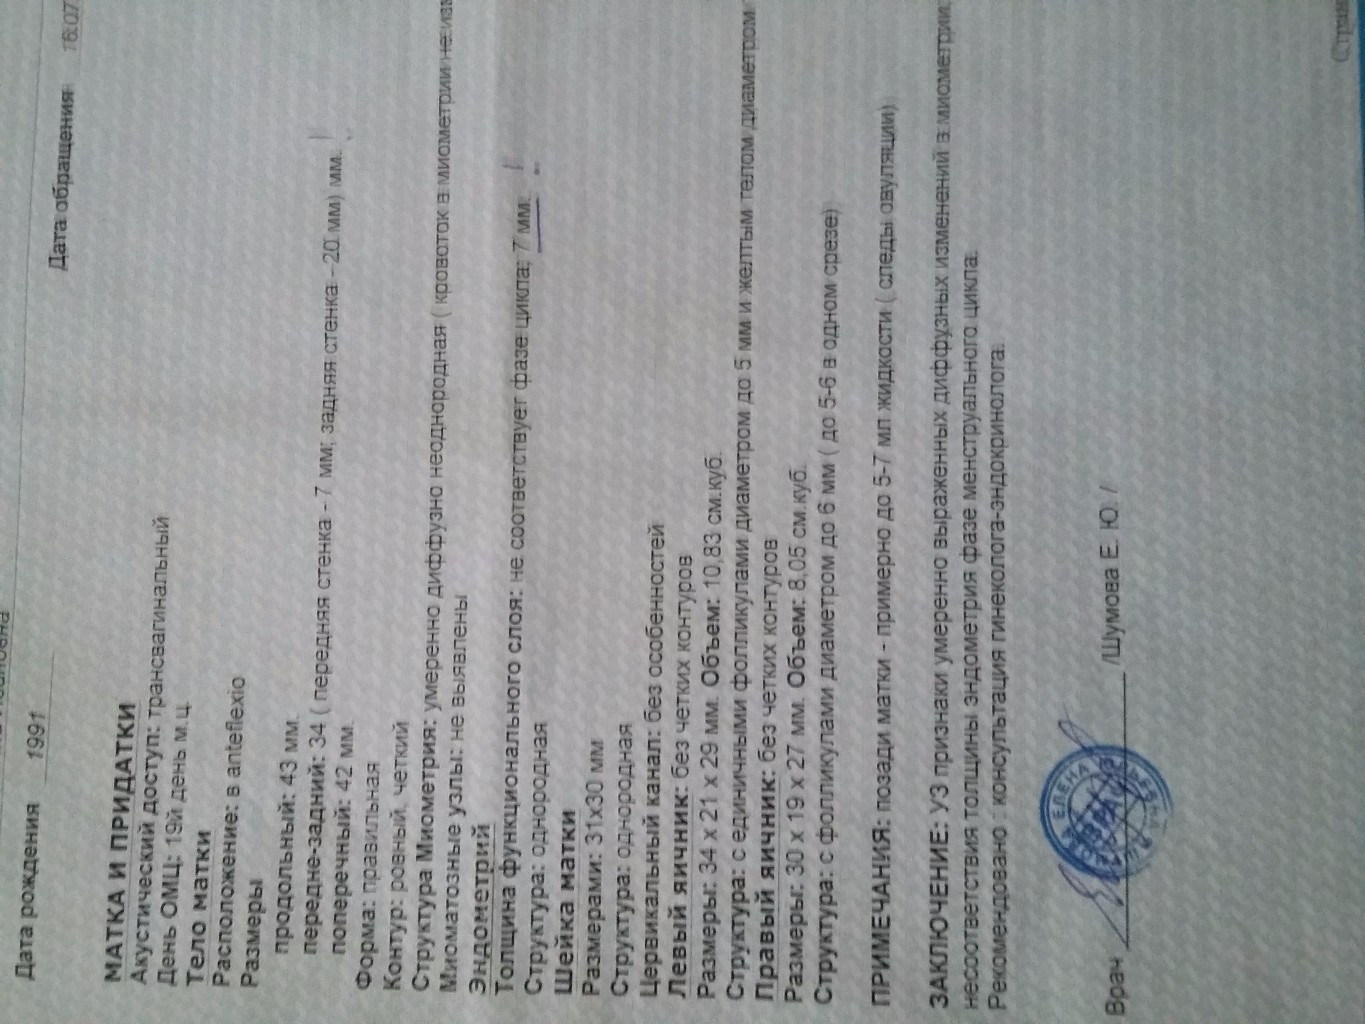

УЗИ малого таза

УЗИ органов малого таза в норме

Почему разные заключения на УЗИ?